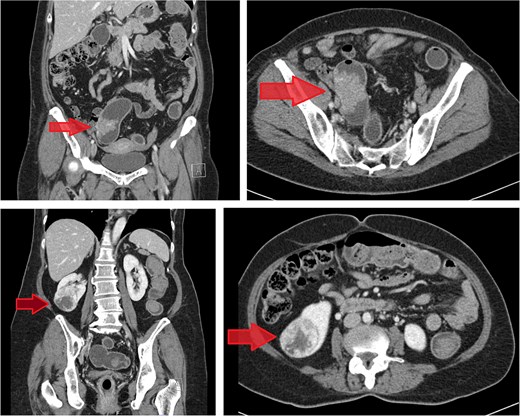

CT scan of the abdomen revealed a short segment of irregular, circumferential wall thickening at the distal descending colon, measuring 1.8 cm in thickness and extending 4.8 cm in length. Moreover, it was associated with an adjacent soft tissue lesion and perilesional fat stranding. Chest CT imaging demonstrated the absence of lymph node enlargement and pulmonary metastatic lesions. Incidentally, a 6.6 cm heterogeneous, hypervascular mass was detected in the interpolar region of the right kidney, abutting the anterior renal fascia (Fig. 3).

Contrast-enhanced CT images of case 2. Top-left: Coronal view of the sigmoid colon cancer. Top-right: Transverse view of the CRC. Bottom-left: Coronal view of the RCC. Bottom-right: Transverse view of the RCC.